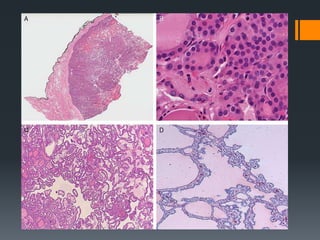

Low magnification to analyze the “texture” of the thyroid

Texture - density of colloid, nuclear size, and contrast

The second step is to decide if the lesion exhibits nuclear

In the absence of nuclear features of PTC, the diagnosis of

unequivocal evidence of capsular and/o vascular invasion.

Architectural and Colloid Changes

Follicular variant PTCs often have

distorted or irregularly shaped

follicles.

 This feature may be focal.

They also usually contain thick,

hypereosinophilic colloid that has a

peculiar scalloped appearance at the

periphery of the follicles